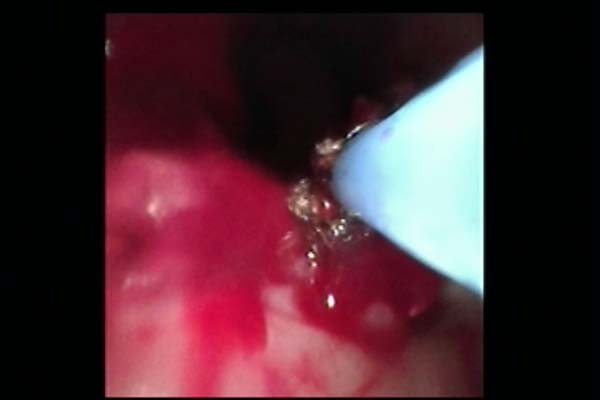

手术中,胸外科团队采用多技术联合操作策略:首先通过常规电子支气管镜完成病变探查与定位,随后置入硬支气管镜建立稳定操作通道,保障术中通气安全。针对气道内增生组织,团队交替使用氩气刀进行精准切除,并应用冷冻治疗仪对残余病灶进行消融与止血。最后在硬镜支撑与细支气管镜引导下,完整取出原有气管支架,未对气道黏膜造成附加损伤。

图2 术中氩气刀治疗